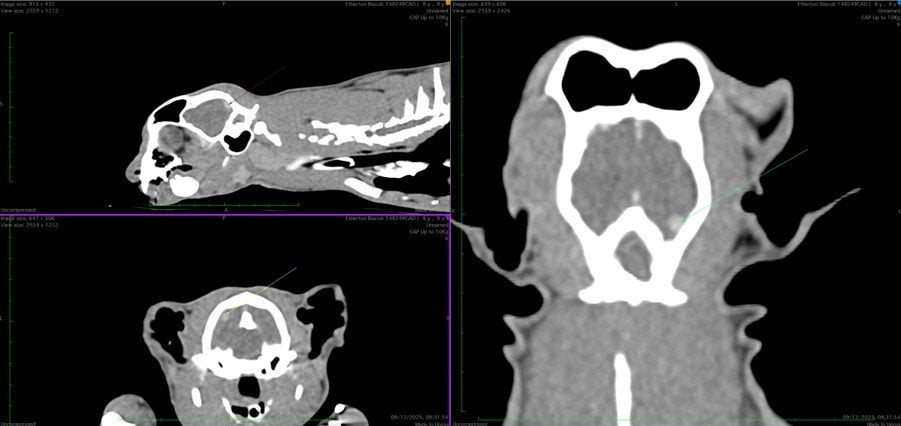

A CT scan showed Biscuit had swelling on his larynx and a 1cm lesion on the brain, which turned out to be a feline meningioma.

The eight-year-old then underwent an intricate one-hour procedure to extract the mass, during which part of his skull was removed.

Experts said the rare procedure, which required 3D mapping Biscuit's brain, was like "removing a pea from a tennis ball".